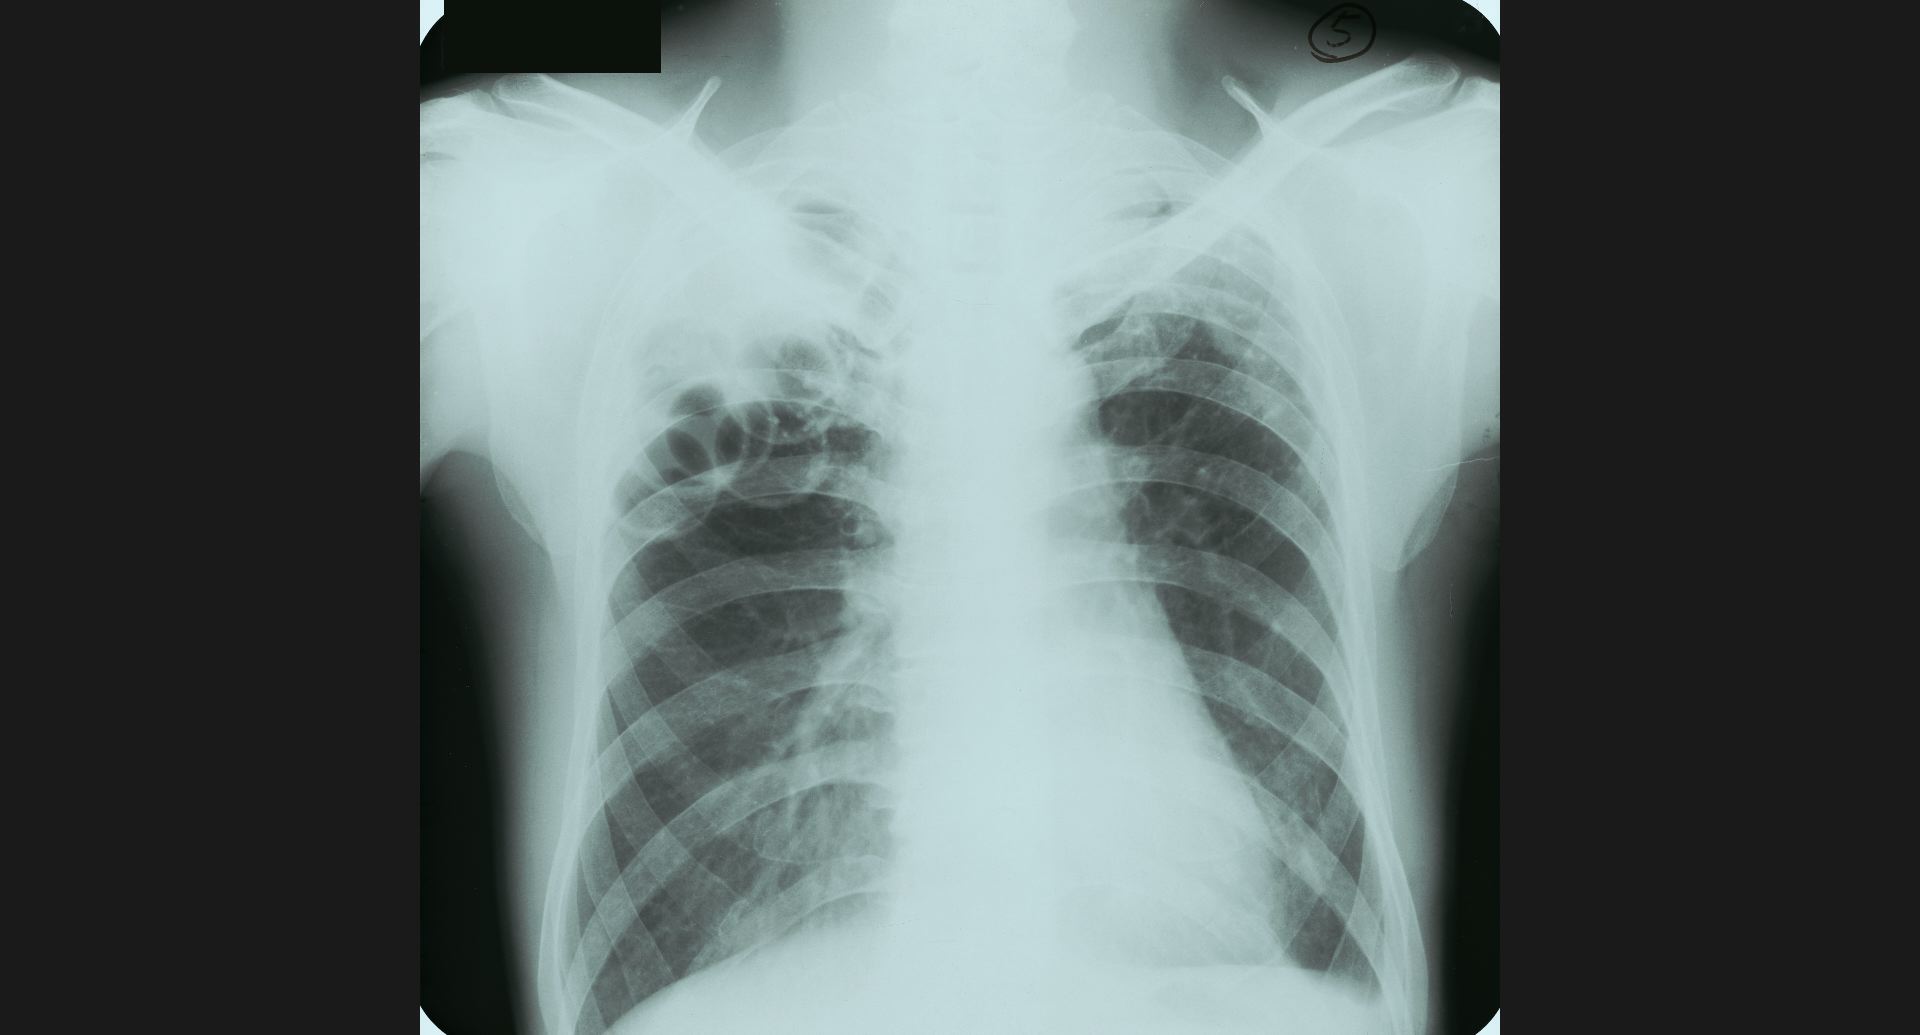

fig.9(94KB)

:Pneumoconiosis細かい斑状陰影。